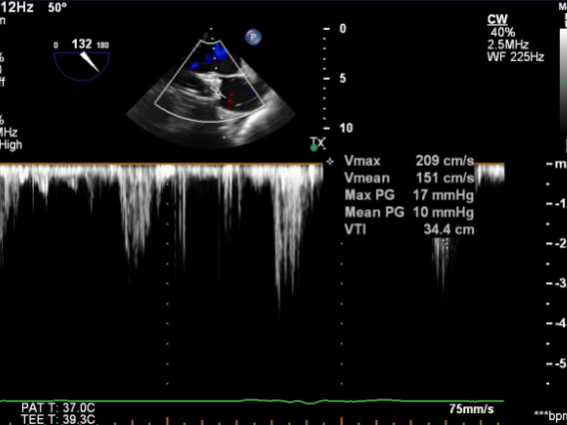

图2.CDFI示主动脉瓣血流信号呈“五彩”样,CW示过瓣流速明显增快

图6.TEE提示未见瓣周漏,CW示过瓣流速较术前明显下降